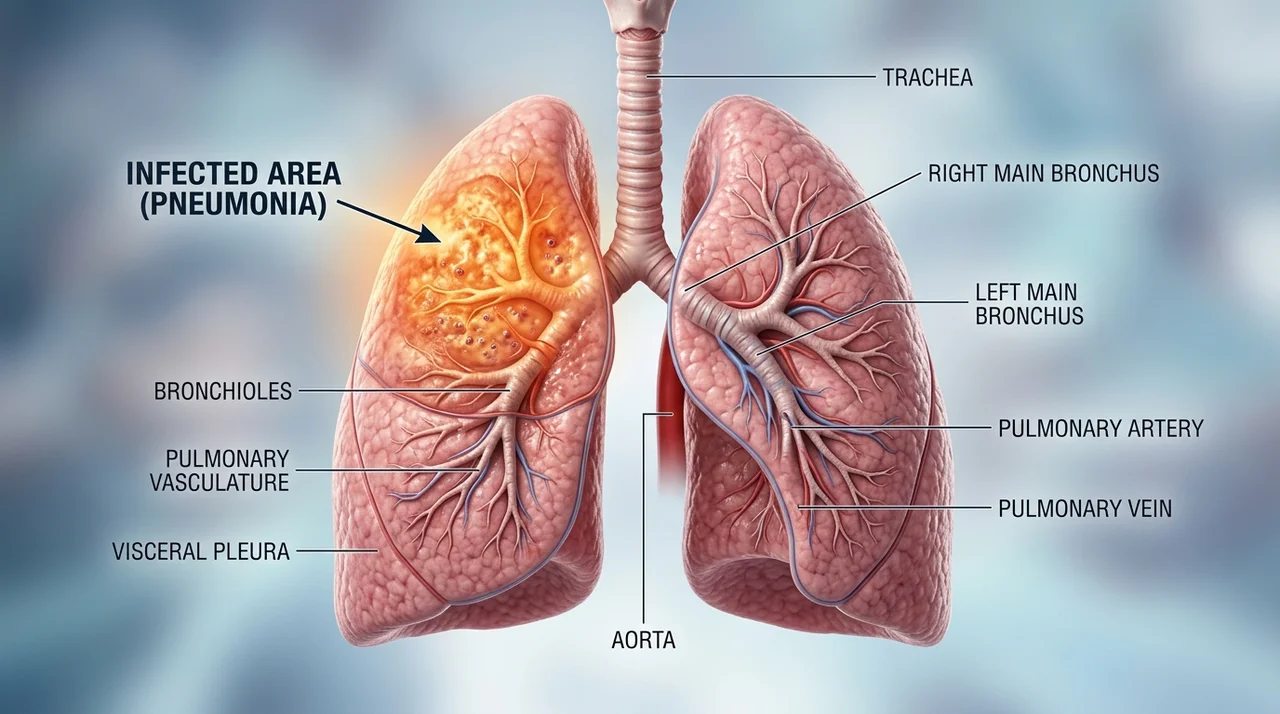

코로나 후유증은 특정 장기에만 국한되지 않고 전신에 걸쳐 다양하게 나타납니다. 크게 호흡기, 신경계, 전신 증상으로 나눌 수 있습니다.

| 호흡기 증상 | 만성 기침, 호흡 곤란, 가래 | 계단을 오르거나 가벼운 활동 시 숨이 참 |

- 심한 호흡 곤란: 가만히 있어도 숨이 차거나 입술이 파래지는 청색증이 나타날 때 (폐렴 또는 폐섬유화 가능성)